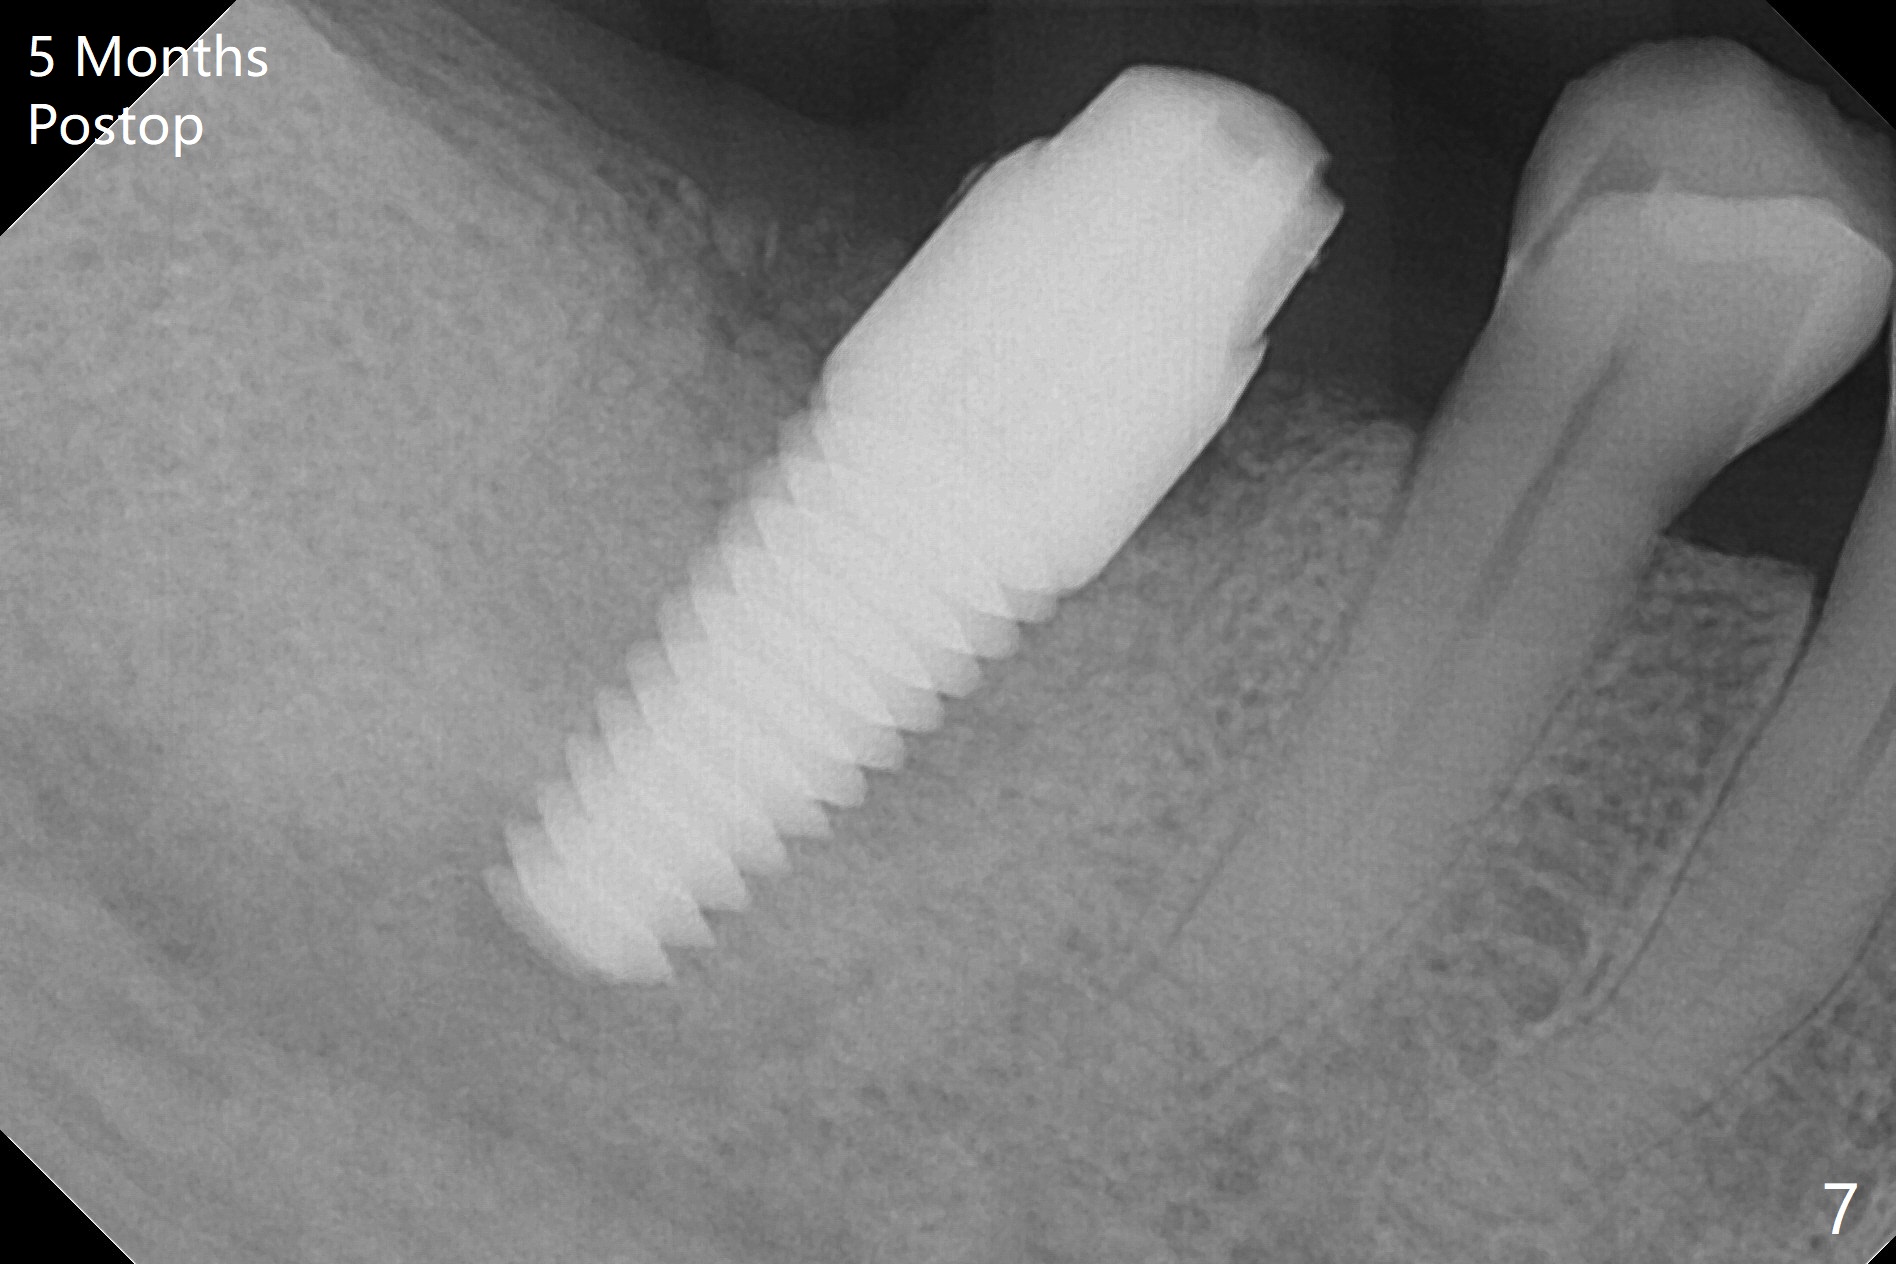

After extraction of the tooth #30 and curettage, the septum becomes so thin that the most coronal portion has to be removed with Rongeur and surgical fissure bur (bone height reduction). Initial osteotomy depth is ~ 4 mm from the flattened septum (Fig.1 (yellow dashed line: apical end of the osteotomy)). Following sequential osteotomy (with intact osteotomy wall), a 6x17 mm tap is placed with apparent clearance from the Inferior Alveolar Canal (Fig.2). When the same size implant is placed with 60 Ncm (Fig.3), the nervous patient feels that the implant is too long (causing pain). CT (Fig.4) and panoramic X-ray (Fig.5) show limited clearance (1.4 mm), but compression of the canal due to high torque could not be ruled out. Since limited amount of the native bone (4.1 mm) for primary stability, the implant is not backed up immediately. Vanilla graft is placed after fabrication of an immediate provisional (Fig.6 *). In brief, immediate implant should be avoided when the septum is thin or the native bone is less than 5 mm (3 mm for primary stability; 2 mm for clearance). In fact the implant has to be untorqued 4-5 times of turn to relieve pain nearly 1 month postop. The patient returns for impression 5 months postop (4 months post implant back up, Fig.7). When the abutment is changed to 5x5 mm and prepared, she reports earache (residual nerve damage?). The patient has had the similar complaint 9 months postop; it appears that there is radiolucency distally (Fig.8 >, as compared to radiopaque mesially (*)). The distal gingiva is tender. With a remade permanent crown, oral hygiene instruction is provided. If necessary, CBCT is taken with possible bone graft.